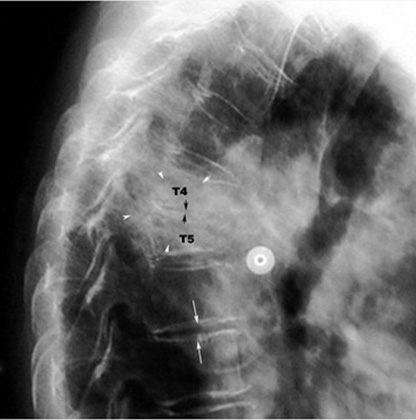

Tuberculosis Spine with gibbus

• Black arrows point to narrowed disc space and loss of end plates.

• White arrows point to normal disc space and end plates.

• White arrowheads point to soft tissue mass.

• T4 and T5 are collapsed.